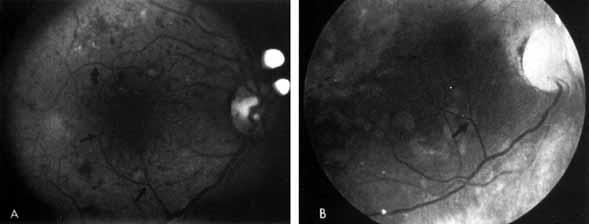

As demonstrated by increased latency and decreased amplitude of the visual evoked potential, many patients with diabetes without retinopathy have subclinical optic neuropathy.269,270 In addition, patients with diabetes can develop two types of acute optic neuropathy. The first, anterior ischemic optic neuropathy (AION) is identical to that seen in patients without diabetes. The patients report a sudden decrease in visual acuity or a sudden visual field loss.271–273 The main ocular finding is a “pale swelling” of the optic nerve head with, considering the degree of disc edema, very few hemorrhages (Fig. 27). On fluorescein angiography segmental nonfilling or slow filling is seen (Fig. 27). An afferent pupillary defect (Marcus Gunn) is nearly always present. Visual fields commonly show altitudinal or nerve fiber bundle defects. The disc progresses to optic atrophy (Fig. 27), and improvement in visual function is rare.

Fig. 27 A. Right eye: ischemic optic neuritis. Note pale swelling of optic disc and blurring of disc margins. Left eye: normal disc. B. Fluorescein angiogram. Note poor filling on disc inferotemporally as compared with the rest of the disc. C. Right eye 6 months after optic neuritis. Note slight pallor.